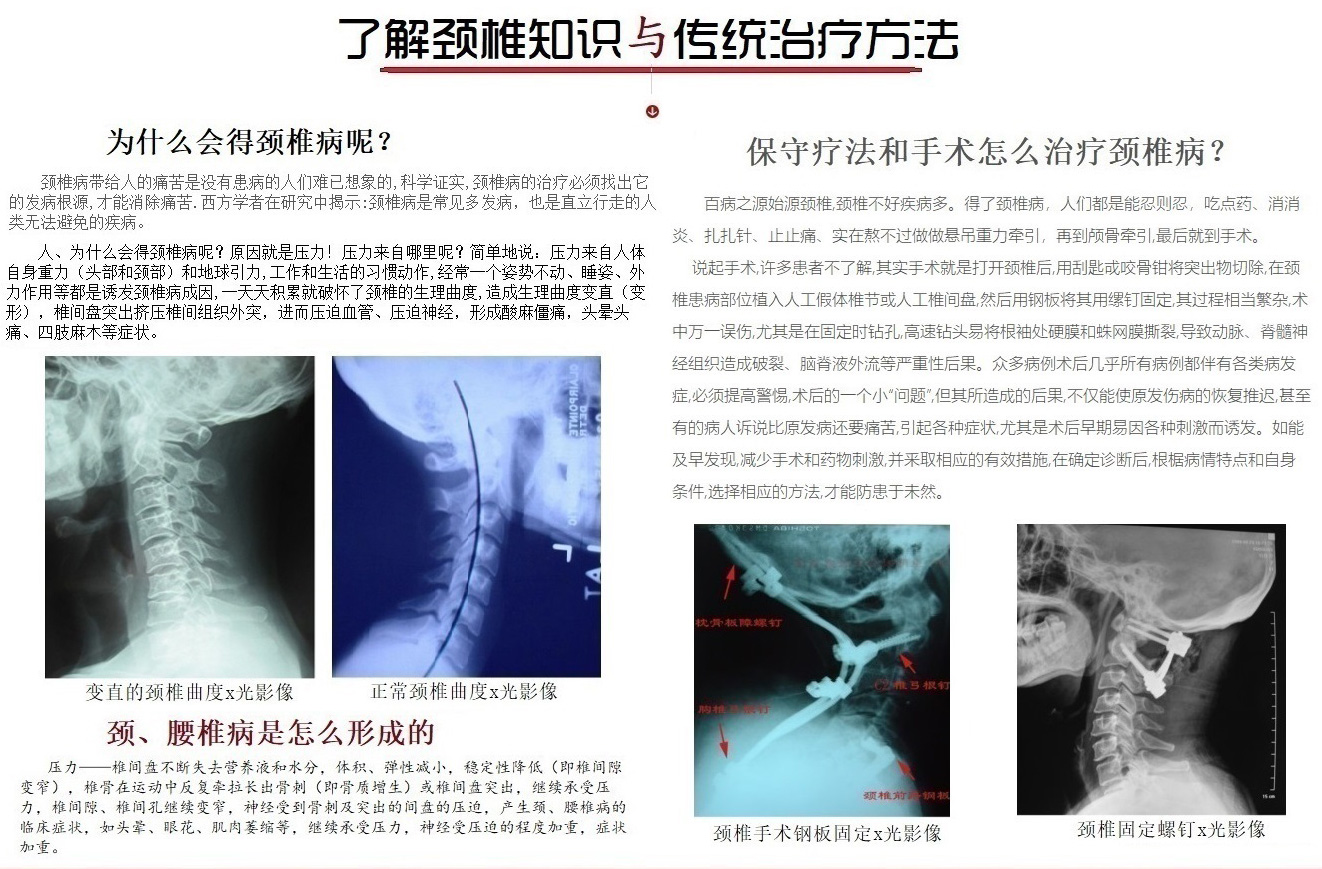

颈椎病带给人的痛苦是没有患病的人们难已想象的,科学证实,颈椎病的治疗必须找出它的发病根源,才能消除痛苦.西方学者在研究中揭示:颈椎病是常见多发病,也是直立行走的人类无法避免的疾病。

人、为什么会得颈椎病呢?原因就是压力!压力来自哪里呢?简单地说:压力来自人体自身重力(头部和颈部)和地球引力,工作和生活的习惯动作,经常一个姿势不动、睡姿、外力作用等都是诱犮颈椎病成因, 一天天积累就破怀了颈椎的生理曲度,造成生理曲度变直(变形),椎间盘突出挤压椎间组织外突,进而压迫血管、压迫神经,形成酸麻僵痛,头晕头痛、四肢麻木等症状。

压力——椎间盘不断失去营养液和水分,体积、弹性减小,稳定性降低(即椎间隙变窄),椎骨在运动中反复牵拉长出骨刺(即骨质增生)或椎间盘突出, 继续承受压力,椎间隙、椎间孔继续变窄,神经受到骨刺及突出的间盘的压迫, 产生颈、腰椎病的临床症状,如头晕、眼花、肌肉萎缩等,继续承受压力,神经受压迫的程度加重,症状加重。

百病之源始源颈椎,颈椎不好疾病多。得了颈椎病,人们都是能忍则忍,吃点药、消消炎、扎扎针、止止痛、实在熬不过做做悬吊重力牵引,再到颅骨牵引,最后就到手术。

说起手术,许多患者不了解,其实手术就是打开颈椎后,用刮匙戓咬骨钳将突出物切除,在颈椎患病部位植入人工假体椎节或人工椎间盘, 然后用钢板将其用缧钉固定,其过程相当繁杂,术中万一误伤,尤其是在固定时钻孔,高速钻头易将根袖处硬膜和蛛网膜撕裂,导致动脉、 脊髓神经组织造成破裂、脑脊液外流等严重性后果。众多病例术后几乎所有病例都伴有各类病发症,必须提高警惕,术后的一个小“问题”, 但其所造成的后果,不仅能使原发伤病的恢复推迟, 甚至有的病人诉说比原发病还要痛苦,引起各种症状,尤其是术后早期易因各种刺激而诱发。如能及早发现,减少手术和药物刺激, 并釆取相应的有效措施,在确定诊断后,根椐病情特点和自身条件,选择相应的方法,才能防患于未然。